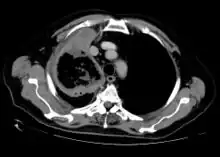

Imaging is often performed, such as CT scan of lungs and sinuses.[38] Signs on chest CT scans, such as nodules, cavities, halo signs, pleural effusion and wedge-shaped shadows, showing invasion of blood vessels may suggest a fungal infection, but does not confirm mucormycosis.[16] A reverse halo sign in a person with a blood cancer and low neutrophil count, is highly suggestive of mucormycosis.[16] CT scan images of mucormycosis can be useful to distinguish mucormycosis of the orbit and cellulitis of the orbit, but imaging may look identical to those of aspergillosis.[16] MRI may also be useful.[39]

CT scan chest of person treated for acute myeloid leukaemia, presented with cough, fever and shortness of breath.